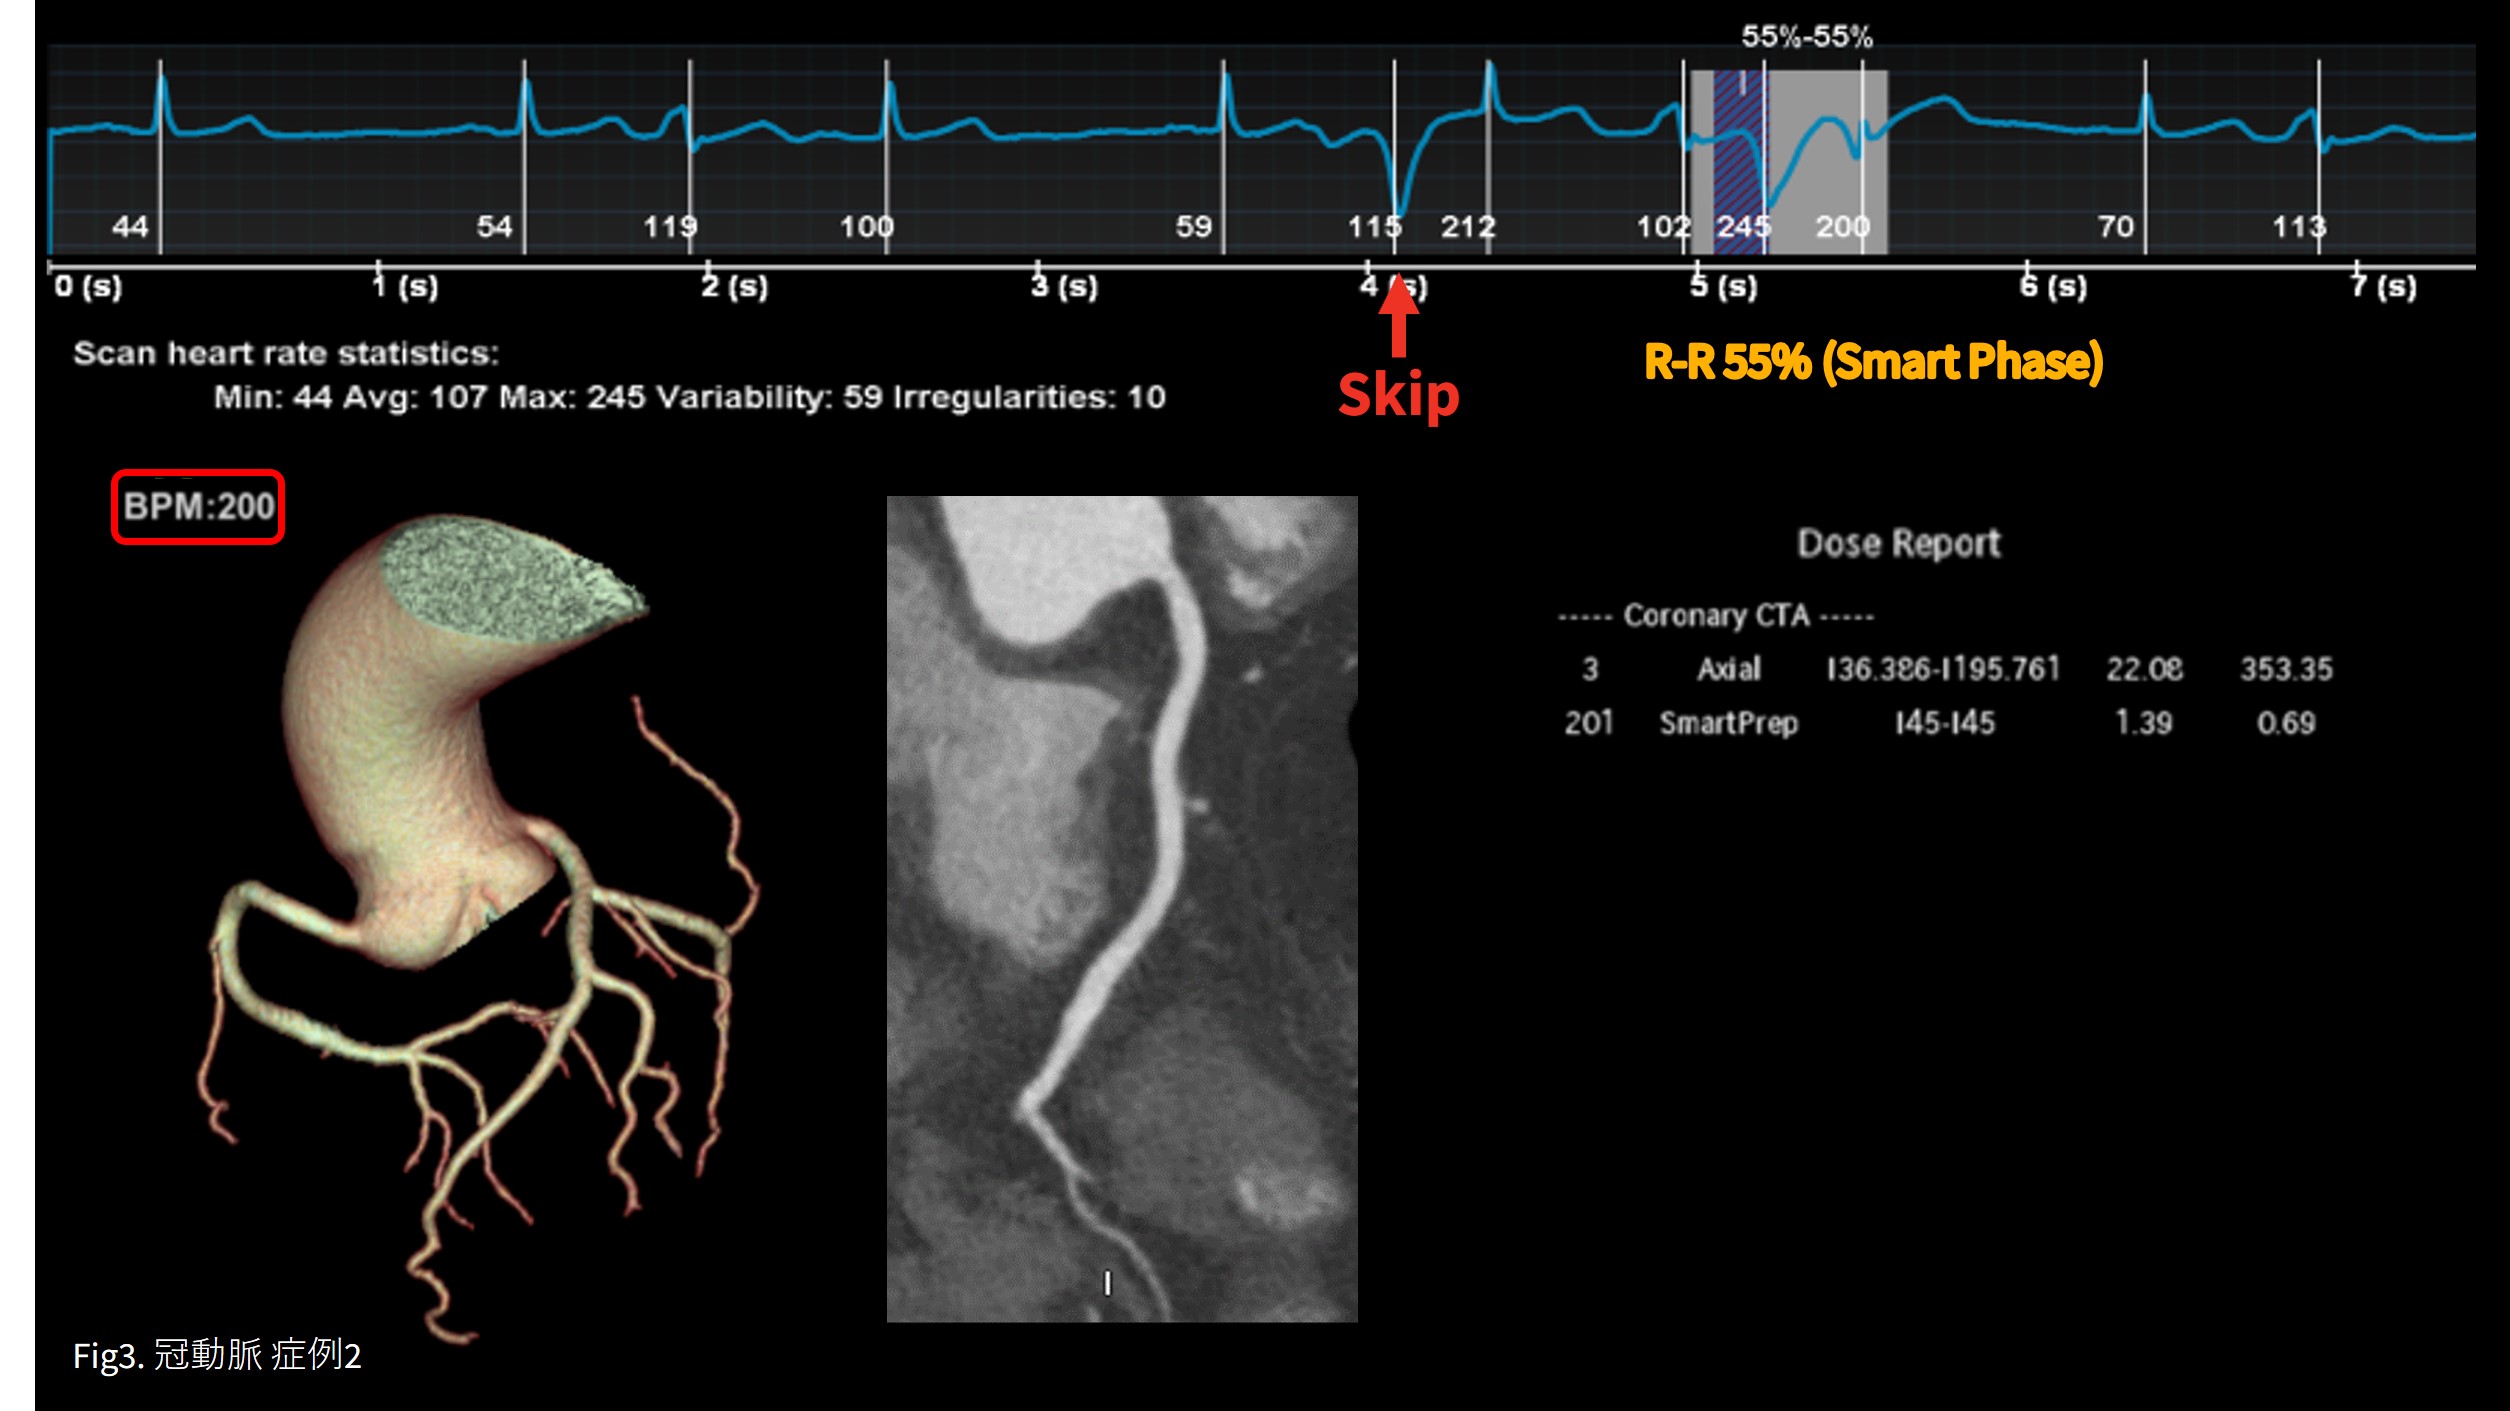

症例2 PVC頻回 Smart Arrythmia Management(SAM)でPVCをskip

造影剤注入後もPVC頻回であったがSAMによりPVCを検知し最適位相を自動収集し撮影できた。心静止位相はSmart PhaseがR-R 55%を選択。 SSF2の効果で画像に全くartifactはなく正常冠動脈と診断しえた。(Fig.3)

PVC精査。負荷心電図は陽性の症例。

PVC頻回であるが洞調律でHR60前後のため βブロッカーは使用せずボーラストラッキング法で撮影。PVC頻回で撮影タイミングが遅れる事が予想されたため注入時間を16秒に延長(通常10~12秒)。